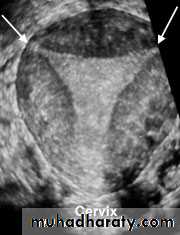

POLYCYSTIC OVARY SYNDROME

Images from women with differing expressions of the four major subtypes of the metabolic syndrome associated with polycystic ovary syndrome (A–D). The images exhibit quite differing ultrasonographic appearances in the size and distribution of follicles within PCOS ovaries. A recent corpus luteum is clearly visible in the ovary in panel (D).

• POLYCYSTIC OVARY SYNDROME